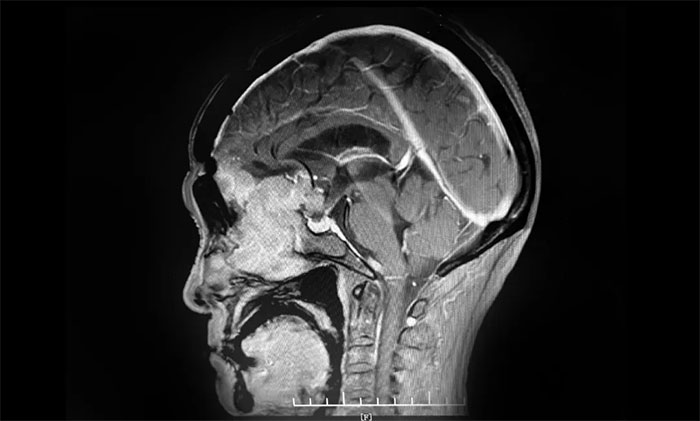

▲ 通過(guò)增強(qiáng)磁共振影像,可見(jiàn)前顱底嗅溝腦膜瘤,體積巨大

頭部增強(qiáng)磁共振影像顯示,患者前顱底嗅溝腦膜瘤體積約6.7*6.4*5.1公分,大如鴨蛋,屬巨大腦膜瘤,瘤體一小部分已經(jīng)延伸侵犯到篩竇內(nèi)。經(jīng)評(píng)估并充分告知手術(shù)風(fēng)險(xiǎn)后,7月9上午,李志強(qiáng)主任為患者實(shí)施巨大腦膜瘤切除手術(shù)。